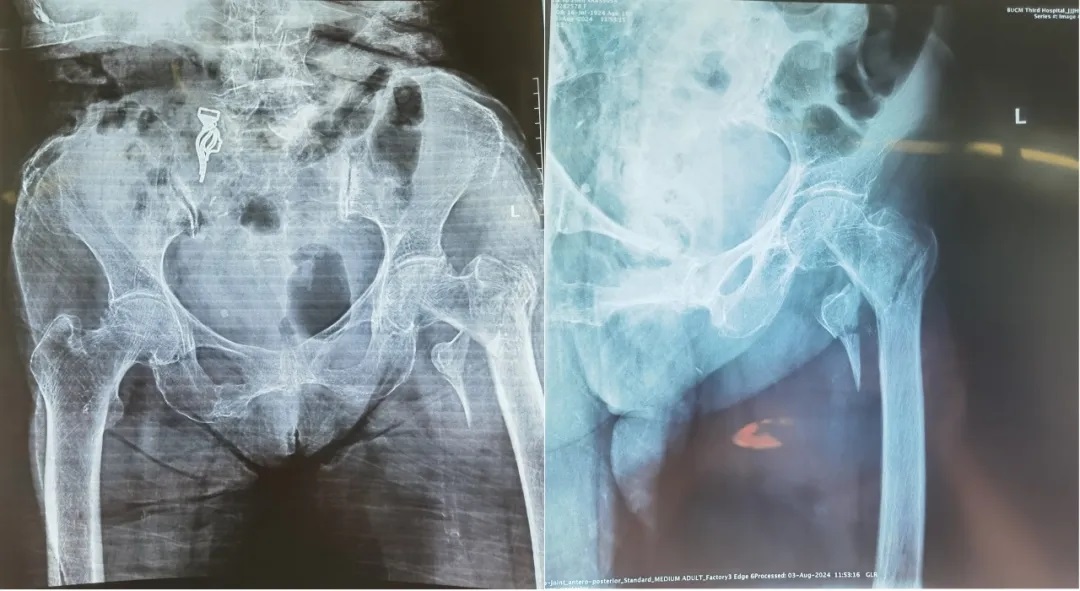

近日,北中医三院医院创伤关节科成功救治了一位百岁老人,其因不慎摔伤导致左髋部骨折。在医院多科室的紧密协作下,老人不仅顺利完成了手术,还迅速恢复了髋部功能。

百岁老人不慎摔伤,左髋部疼痛肿胀,活动受限。拍片结果显示为股骨粗隆间骨折,这一被称为“人生最后一次骨折”的病症,因其高风险的并发症和死亡率,给救治工作带来了巨大挑战。创伤关节科陈卫衡教授、郭盛君主任团队迅速行动,为老人制定了周密的治疗计划。在完善术前检查后,当日下午即办理了住院手续,时间就是生命,每一刻都不容耽搁。

考虑到老人的高龄和身体状况,手术团队选择了微创技术。手术过程中,郭盛君主任团队手法熟练,仅用时53分钟就完成了骨折复位和内固定。麻醉科团队密切监测老人的生命体征,确保了手术的安全进行。术后,创伤关节科的医护人员对老人进行了全天候的密切观察和精心护理。在他们的不懈努力下,老人的恢复情况出乎意料地好。短短几天内,老人便能进行简单的活动,疼痛和肿胀也得到了有效控制。